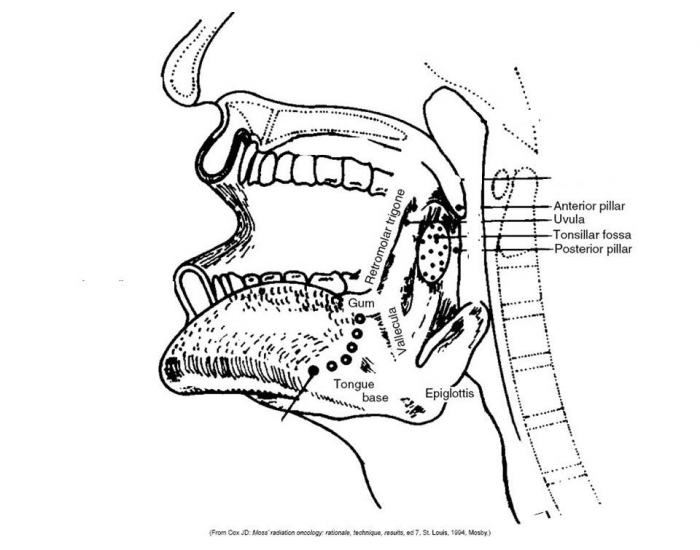

Anatomy Head and Neck Practice Questions. What are the boundaries of the submental triangle and what does it contain? Click the card to flip 👆. a. Body of hyoid bone, anterior bellies of both Diagastrics, Mylohyoid forms floor. b. Contents: 2-4 lymph nodes, veins that unite to form anterior jugular vein. Click the card to flip 👆.

Test your knowledge of the anatomy of the head and neck with this quiz. Explore topics such as the hyoid bone, larynx, swallowing process, temporomandibular joint, muscles of mastication, muscles of the neck, orbit structure, layers of the globe, and eye movement. Sharpen your understanding of these critical anatomical structures and their functions.

Are you looking to test your knowledge of the head and neck region? Take our quiz to see how well you know the anatomy and structures of the face, sinuses, oral cavity, and pharynx. From the blood supply of the scalp to the muscles of the pharynx, this quiz covers a variety of topics with keywords specific to the field. Test your understanding of the structures of the head and neck with our.

Test your knowledge of anatomy with this quiz on the structures and functions of the head and neck. From the eyelids and muscles of the face to the nasal cavities and pharynx, this quiz covers a range of topics related to the head and neck region. Learn about the anatomy of the eyes, nose, mouth, and throat while practicing your ability to recall important terms and functions. Challenge.